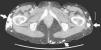

Mujer de 36 años con antecedente de lupus eritematoso sistémico de 21 años de evolución, con afectación hematológica, cutánea y articular. En el estudio inmunológico destacan ANA (título 1:1.000, patrón de fluorescencia homogéneo), anti-DNA, anti-ENA y anti-Ro (SSA) positivos. Presenta múltiples nódulos subcutáneos de consistencia dura en tronco y extremidades de aproximadamente 10 años de evolución, que confluyen en cintura, glúteos y muslos formando extensas placas. A lo largo del último año, refiere la aparición progresiva de una úlcera con exudado seroso sobre una de las lesiones en muslo izquierdo. Los cultivos resultaron positivos para Staphylococcus aureus. La radiografía simple de abdomen (fig. 1) y una tomografía computarizada abdominal (fig. 2) revelaron múltiples calcificaciones extraóseas (flechas) de localización subcutánea. A pesar del tratamiento con diltiazem, las calcificaciones persisten y la lesión ulcerosa presenta una evolución tórpida.